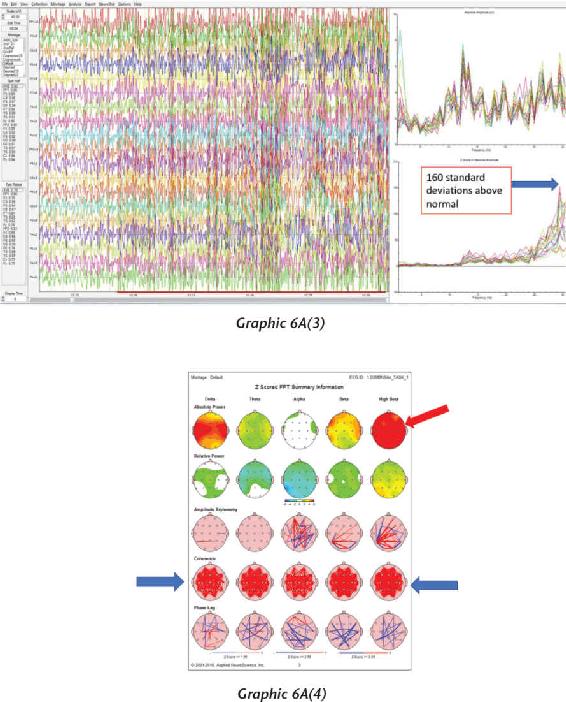

We have thousands and thousands of brain scans that prove those changes were not just imagined in their minds but actually took place in their brains. Several of the students we measured accomplished those changes within four days (the length of our advanced workshops). The scientific teams I’ve assembled have taken brain scan recordings using quantitative electroencephalogram (EEG) measurements before and after workshops as well as real-time measurements during the meditations and practices themselves. I was not only impressed with the changes, but shocked by them—they were that dramatic.

At the end of 2013, something mysterious started occurring. We started seeing brain scan recordings that puzzled the researchers and neuroscientists who came to our events to study my work. The high amount of energy in the brain that we were recording while a student was in certain meditations had never been recorded up until this point. And yet we were seeing these off-the-charts readings again and again.

When we interviewed the participants, they reported that their subjective experience during the meditation was very real and mystical, and that this either profoundly changed their view of the world or dramatically improved their health. I knew in those moments that these participants were having transcendental experiences in their inner world of meditation that were more real than anything they had ever experienced in their outer world. And we were capturing those subjective experiences objectively.

That has become a new normal for us now, and as a matter of fact, we can often predict when these high amplitudes of energy in the brain will occur, based on certain indicators and signs that we have seen for years now. In these pages, I want to demystify what it is to have an interdimensional experience as well as provide the science, biology, and chemistry of the organs, systems, and neurotransmitters that make this happen. It is my hope that this information will give you a road map for how to create such experiences for yourself.